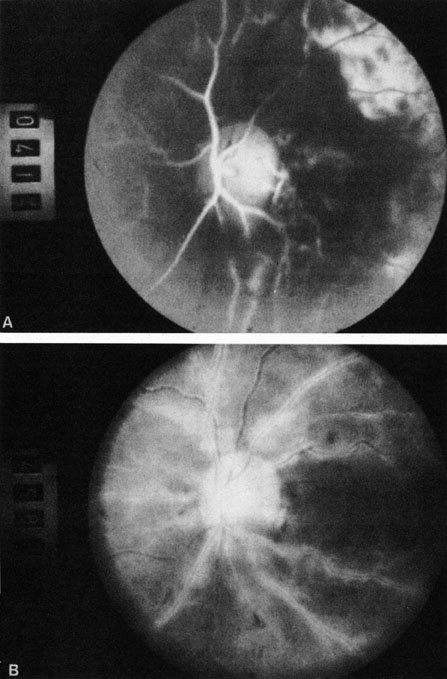

Cilioretinal arteries can be selectively obstructed (Fig. 3). More commonly, however, they occur in association with central retinal vein obstruction.113 When they supply a significant portion of the macula, decreased visual acuity is common. Prognosis for visual outcome in such patients is good. Brown and co-workers114 studied 10 eyes having an isolated cilioretinal artery obstruction. Of those, 60% had an initial visual acuity of 20/40 or better and on follow-up examination, all eyes but one had a best-corrected visual acuity of 20/40 or better.114

Fig. 3. A: Cilioretinal artery obstruction showing opacity of the retina in the area of obstruction. B: The cilioretinal artery has begun to fill after the branches of the central retinal artery but is still not completely filled at this point in the angiogram.

Obstruction of one of the posterior ciliary arteries may result in a whitening of the area of the retina supplied by the involved posterior ciliary artery and the subsequent appearance of patchy pigmentation in the same area. However, in patients with anterior ischemic optic neuropathy secondary to temporal arteritis the retina may appear normal (Fig. 5). In the case of either the medial posterior ciliary artery or the lateral posterior ciliary artery, the area involved is the size of approximately half of the choroid.121–123 In the case of a long posterior ciliary artery, the temporal side of the eye including the macula is involved.121

Fig. 5. A: Ischemic optic neuropathy in a patient with giant cell arteritis. B and C: Intravenous fluorescein angiography demonstrates delayed filling of the lateral posterior ciliary artery.

We have seen several patients with anterior ischemic optic neuropathy with suspected temporal arteritis where the Westergren sedimentation rate and C-reactive protein were normal and the intravenous fluorescein angiogram helped confirm the diagnosis (Fig. 5).